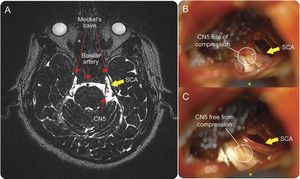

Compression caused by Spinocerebellar Ataxia (SCA), a group of hereditary ataxias that are characterized by degenerative changes in the cerebellum and (potentially) the spinal cord. SCA is inherited in an autosomal dominant matter; however the term “spinocerebellar” may be found with other diseases, such as the autosomal recessive spinocerebellar ataxias (SCAR). Question: What are some symptoms of SCA? Also what kind of imagining is being used above?